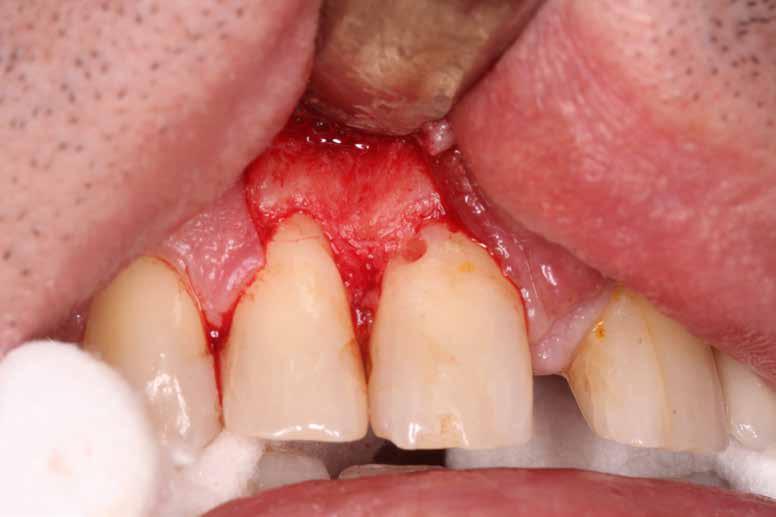

A megfelelő vizuális kontroll és az izolálhatóság kedvéért lebenyt alakítottunk [4. kép]. Így az abszolút izolálás már kivitelezhető volt és kofferdám izolálásban kezeltük a léziót [5. kép]. Mivel az elváltozás nem látható területen helyezkedett el, illetve a kavitás kis kiterjedését figyelembe véve kalcium-szilikát bázisú anyagot választottunk a restauráláshoz (Biodentine, Septodont) [6. kép]. Miután letelt a választott anyagunk kötési ideje (12 perc), zártuk a lebenyt [6. kép]. Páciensünk azóta is panaszmentes, kétéves kontrollon állapota rendben volt [7. és 8. kép].

11. kép: Kiindulási állapot.